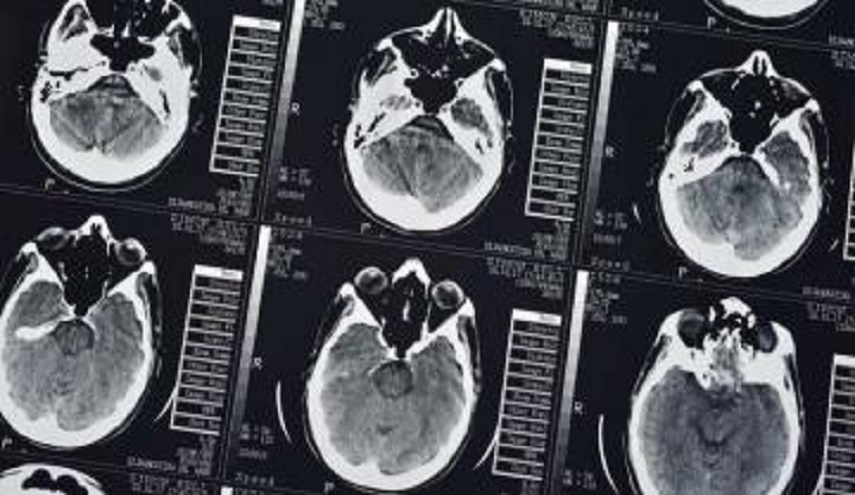

علوم وتكنولوجيا_الكوثر: نشرت وكالة الأنباء الصينية شينخوا، أن الذكاء الاصطناعي الصيني “BioMind”، تفوق على أفضل الأطباء في مسابقة من مستويين لتشخيص أورام الدماغ والتورم الدموي.

وشخص نظام الذكاء الصيني 225 حالة من أورام الدماغ خلال 15 دقيقة وبدقة تشخيص بلغت نسبتها 87%. في حين شخص 15 طبيبا من أمهر أطباء الأورام في الصين هذه الحالات بدقة بلغت 66% فقط. وأضافت الوكالة أيضا أن الذكاء الاصطناعي شخص حالات لمرضى التورم الدموي بنسبة نجاح بلغت 83% وبدقة أعلى من تشخيص أمهر الأطباء بنسبة 20%.